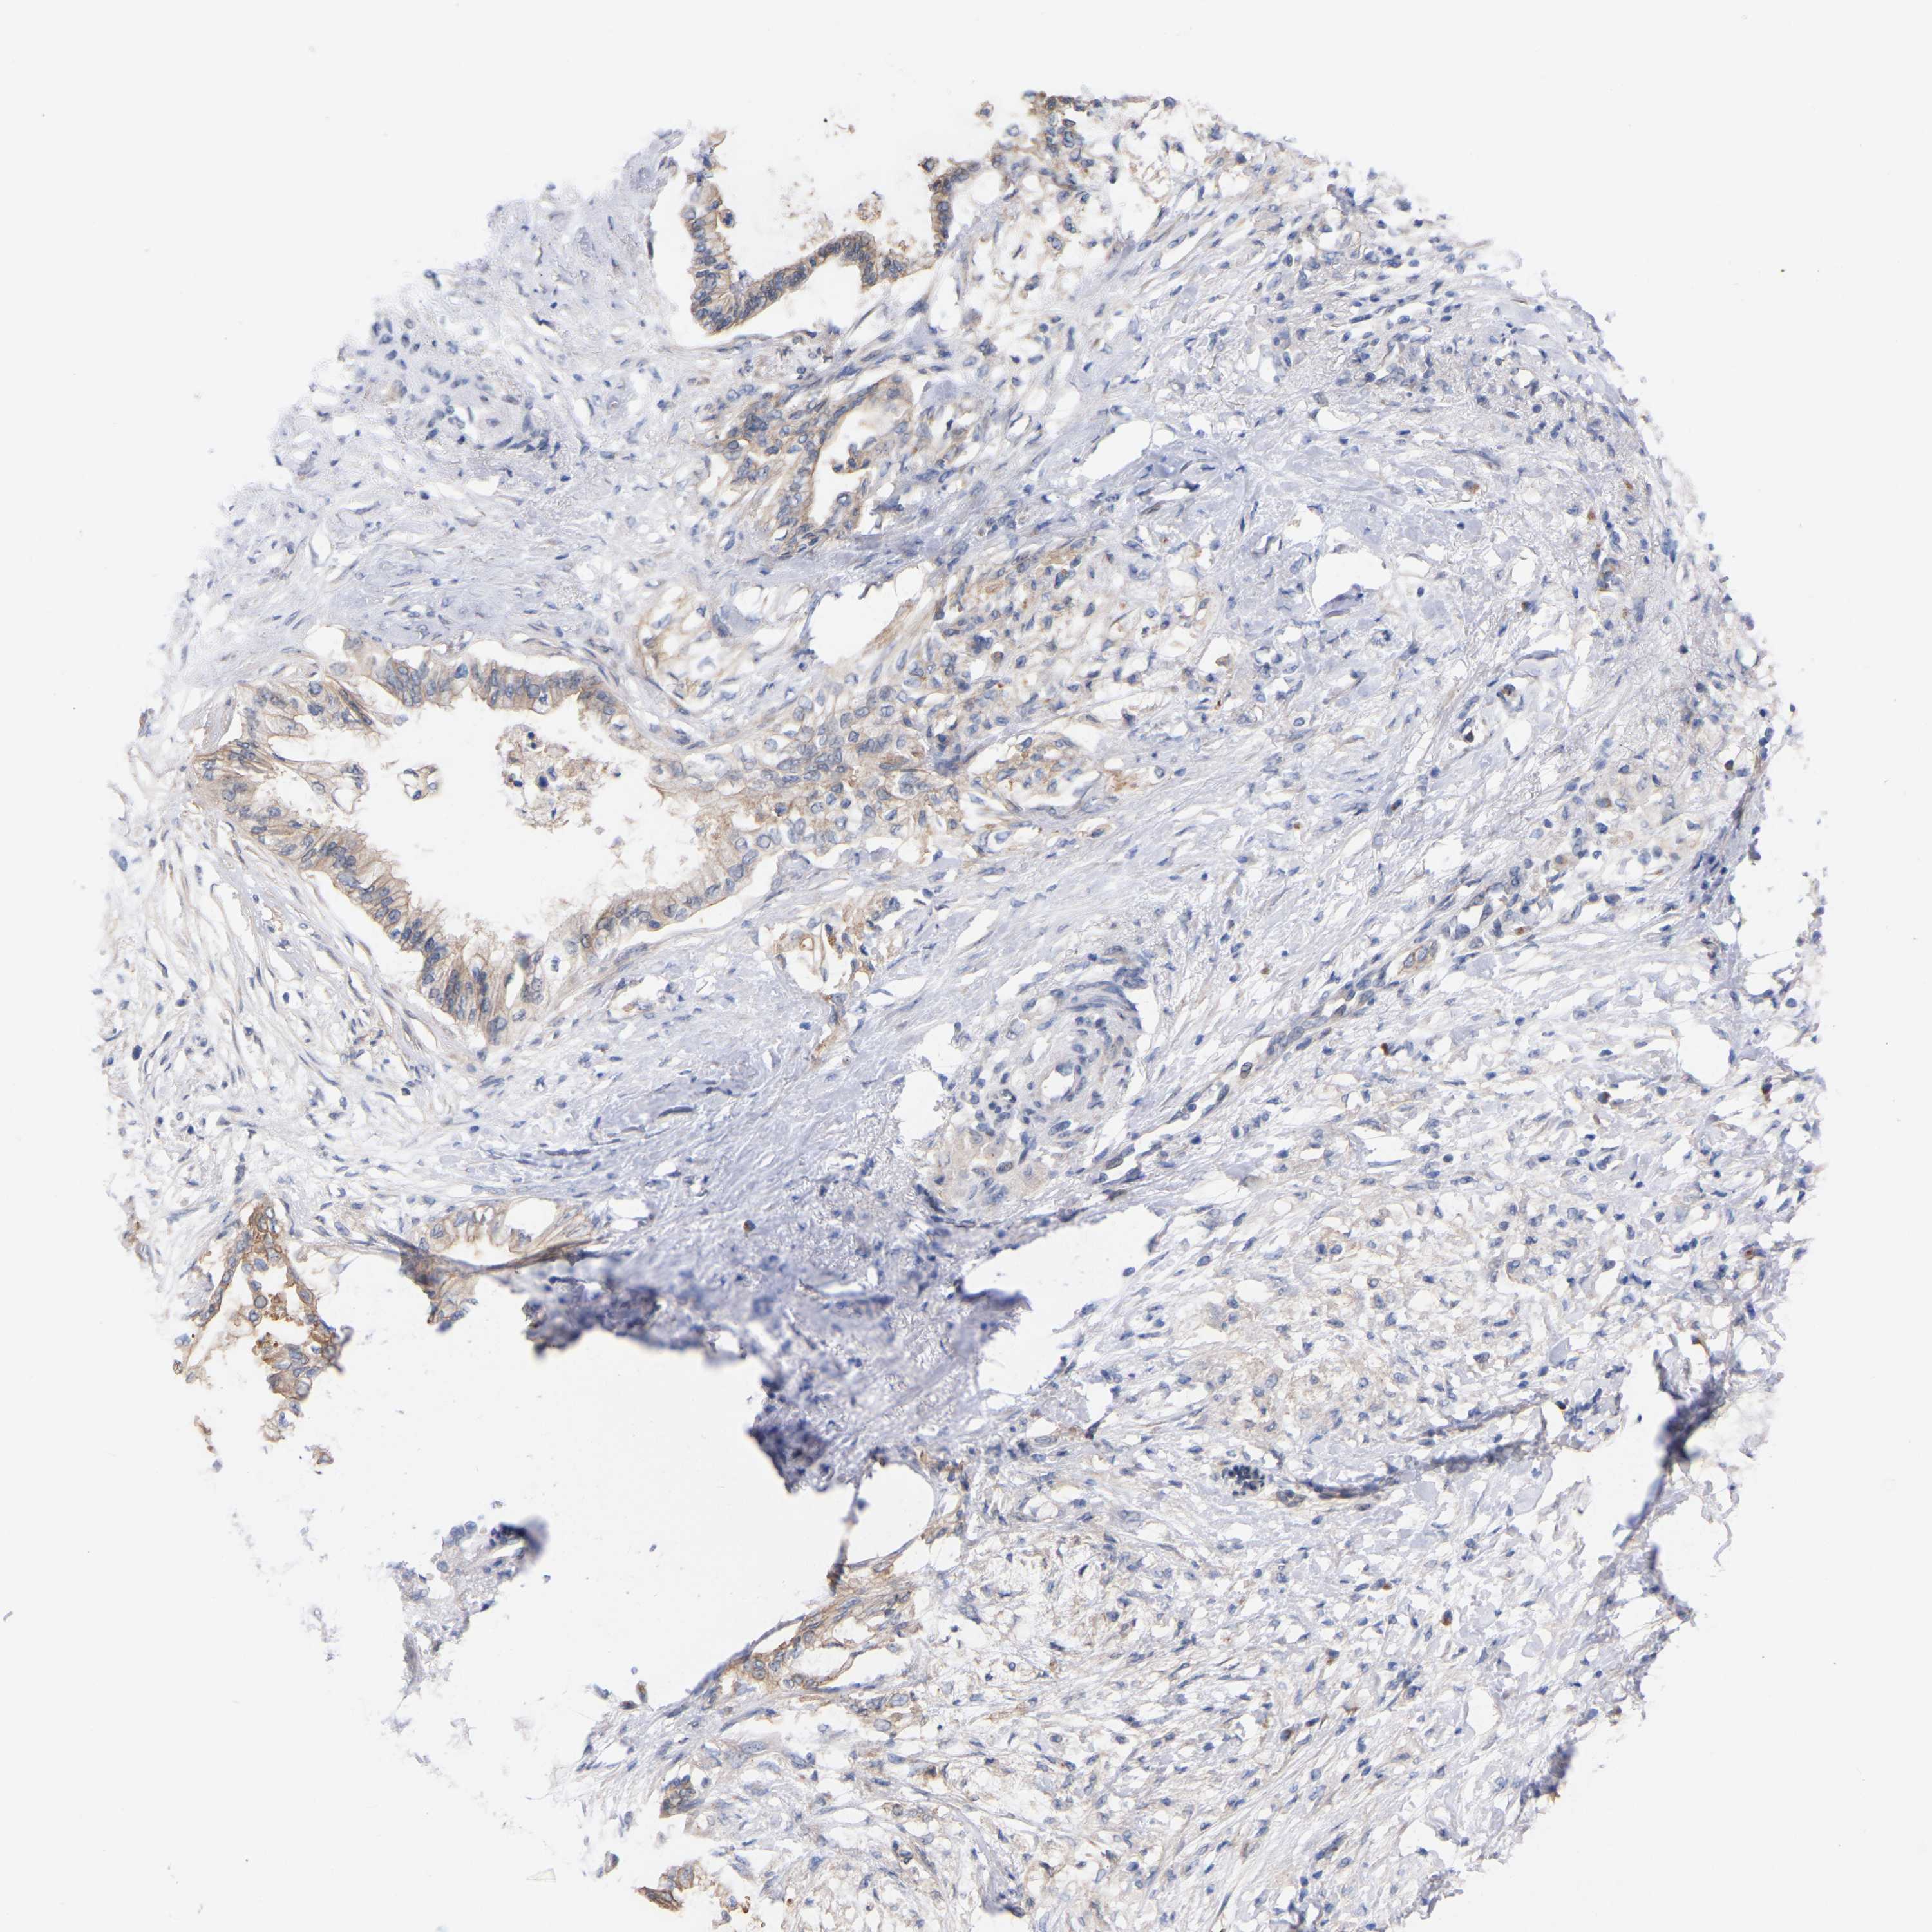

PANCREATIC CANCER - Protein expressioni

A mouse-over function shows sample information and annotation data. Click on an image to view it in a full screen mode. Samples can be filtered based on level of antibody staining by selecting one or several of the following categories: high, medium, low and not detected. The assay and annotation is described here.

Note that samples used for immunohistochemistry by the Human Protein Atlas do not correspond to samples in the TCGA dataset.

Antibody stainingi

Antibody staining in the annotated cell types in the current human tissue is reported as not detected, low, medium, or high, based on conventional immunohistochemistry profiling in selected tissues. This score is based on the combination of the staining intensity and fraction of stained cells.

Each image is clickable and will lead to virtual microscopy that enables deeper exploration of all samples and also displays staining intensity scores, fraction scores and subcellular localization as well as patient and tissue information for each sample.

Antibody HPA001818

Antibody CAB018352

Adenocarcinoma, NOS

Adenocarcinoma, metastatic, NOS